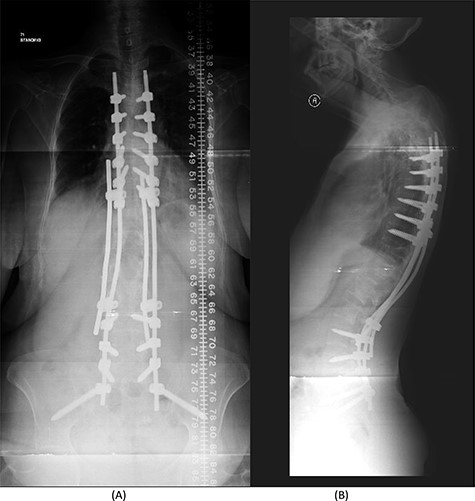

(A) AP lumbar spine X-ray demonstrating final fixation from T5-S2-alar-iliac screws. (B) Lateral spine X-ray.

Over a year after the surgical procedure with the bridging technique, the patient presented with a new-onset lower back pain after hearing a crack. X-ray showed bilateral rod fractures and the CT scan showed re-ossification of the involved levels (T11–L3; Fig. 5). An MRI showed complete recovery of the infection without cord compression (Fig. 6). At this stage, we elected to proceed with a revised surgical intervention that involved adding bilateral pedicle screws at the re-ossified vertebrae (T11, T12, L2 and L3). The patient tolerated the surgery well and had a normal neurological examination postoperatively. CT scan post revision demonstrated fixation of T5 to S2 alar-iliac with a well-fixed construct. CRP level upon discharge was 7 mg/l and procalcitonin was <0.02 ng/ml. The patient was recovering well at follow up 1 year later (Fig. 7).

The patient underwent a revised form of posterior spinal fixation from T5 to S2 using a bridging technique and double rods on each side to allow healing and re-ossification of the vertebra with removal of the screws in T11–L3. Due to the instability of the bridging technique, the rods were broken and posterior fixation was deemed a failure. The patient underwent a revision of fixation with insertion of pedicle screws in all levels and a single rod on each side (Fig. 7). In this stage, complete eradication of the infection was achieved and there was no collection.